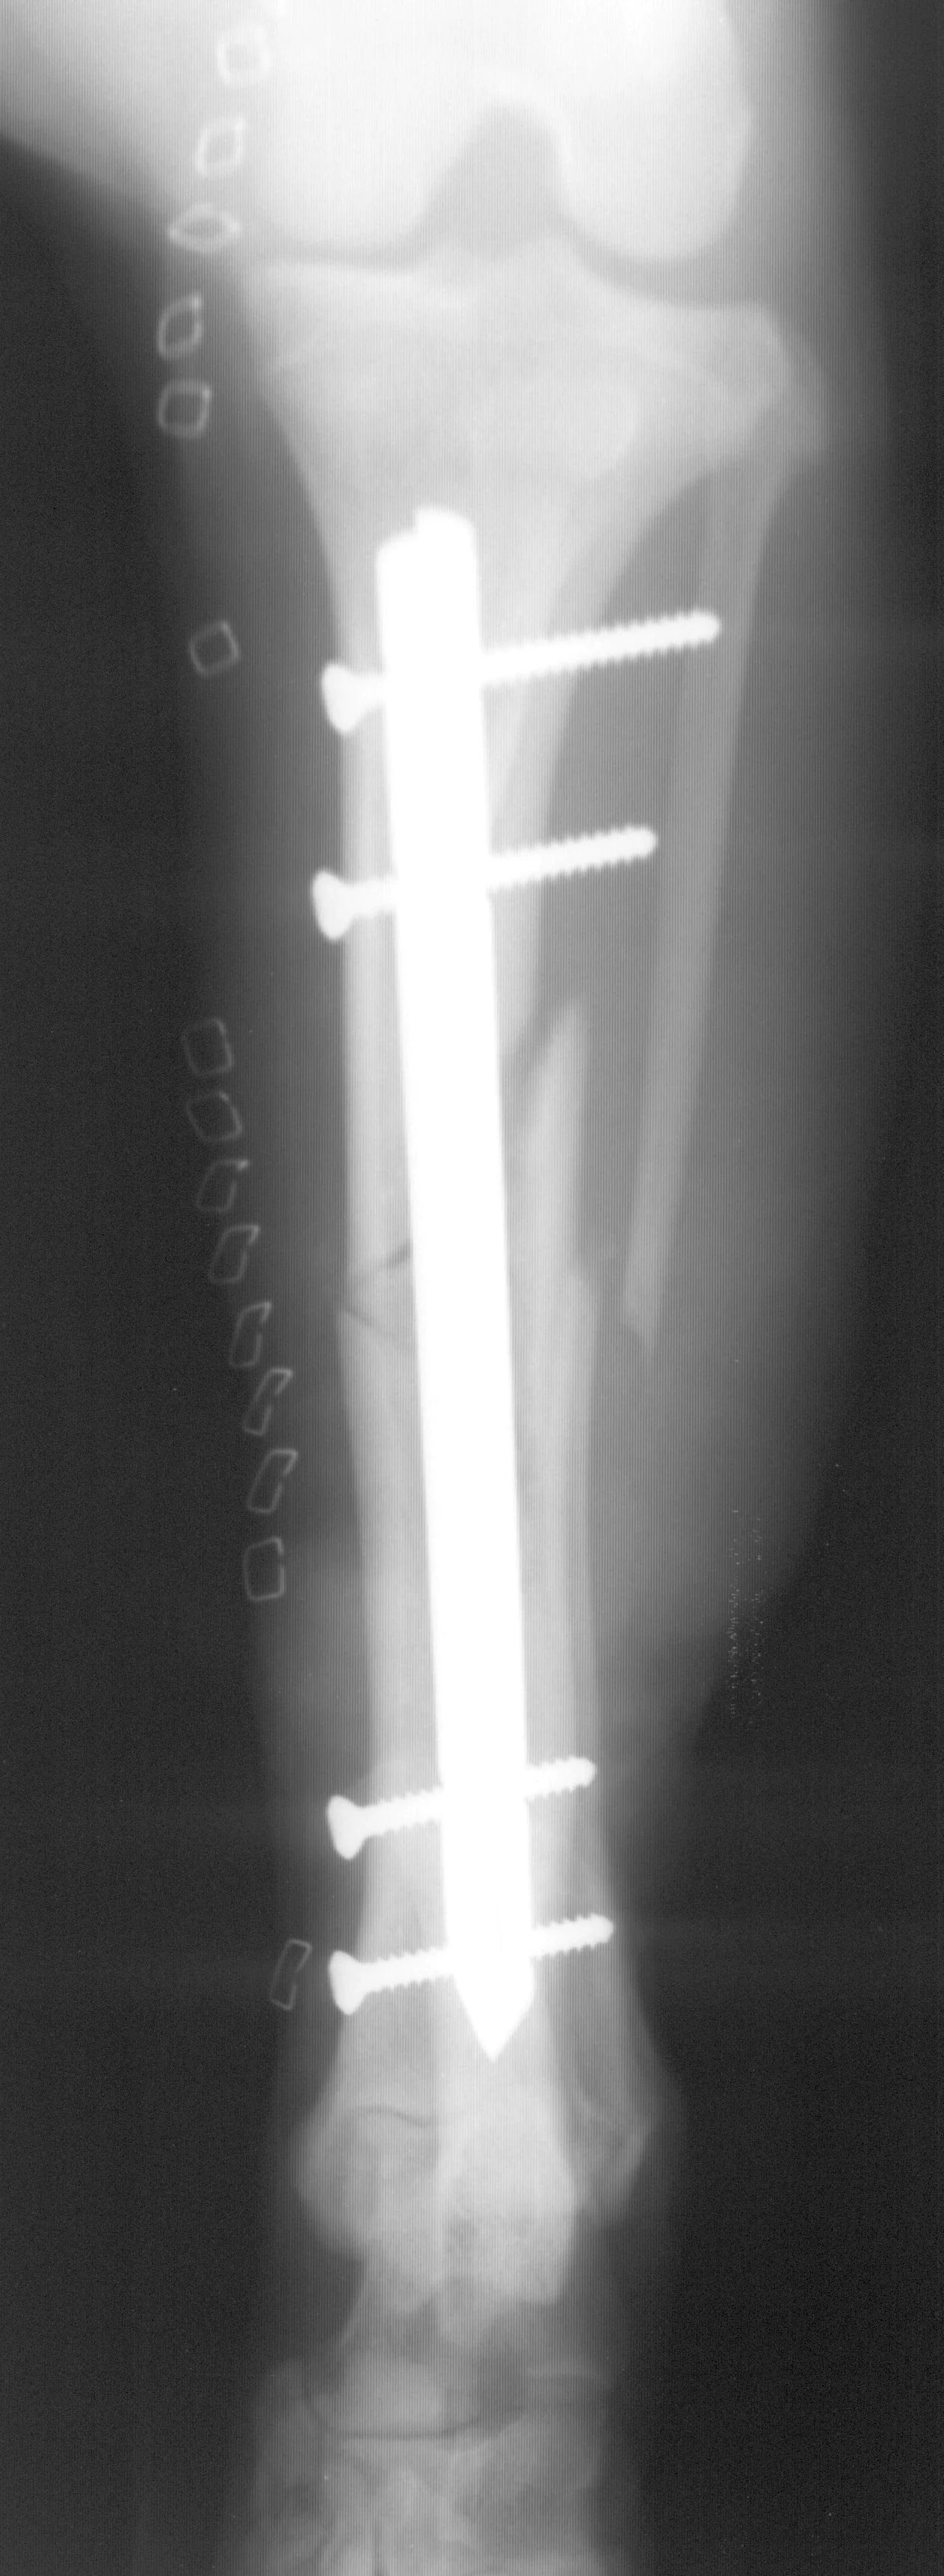

The interlocking-nail system (Innovative Animal Products, Rochester, MN) is another effective implant system for biologic management of comminuted fractures in dogs and cats.1 The interlocking nail is a modified Steinmann pin having transverse holes designed to accommodate screws or bolts. The addition of screws or bolts increases the ability of the pin to resist rotational and compressive forces at the fracture site (Figures 2A, B). This type of fixation is commonly used for stabilization of fractures of the femur and tibia in humans.

Interlocking nails are used in dogs and cats for repair of fractures of the humerus, femur, and tibia. The interlocking-nail system is less expensive than a bone-plate system but has similar biomechanical properties.8 Interlocking nails are easy to apply and are a good option for general practitioners who do not want to invest in a bone-plate system.

Fractures managed using interlocking nails and biologic technique develop extensive bridging callus and early return to function. A minimally invasive surgical approach (note the surgical skin staples) was made to this fracture to minimize disruption of the blood supply to the bone fragment. The fracture fragments quickly become incorporated in the callus if soft tissue attachments can be maintained.

Healing of the comminuted tibial fracture shown in Figures 2A and 2B after stabilization using an interlocking nail system. This fracture reached bony union in 8 weeks.